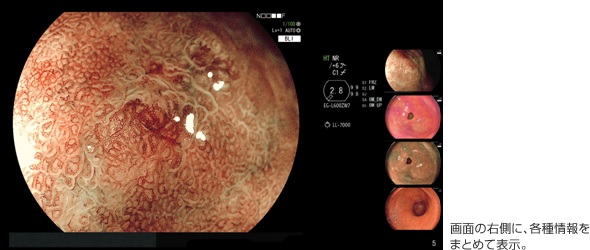

ユーザビリティにもこだわった。ワイドモニターに対応し、検査画像を大画面で観察することができるようになった。また、従来は、スコープ操作部のスイッチの設定内容などの情報が画面上に点在して表示されていたが、本製品では画面の右側にまとめて表示されるようになり、必要な情報が探しやすくなった。さらに、検査中に撮影した直近4枚の画像もインデックスとして画面の右端に表示され、画面を切り替えることなく、撮影画像をスムーズに参照することが可能。検査時間の短縮が期待される。

ワイドモニターに対応しており、検査画像を大画面で観察することができる。また、従来は、スコープ操作部のスイッチの設定内容などの情報が画面上に点在して表示されていたが、本製品では画面の右側にまとめて表示されており、必要な情報を探しやすくなった。さらに、検査中に撮影した直近4枚の画像もインデックスとして画面の右端に表示されている。これにより、画面を切り替えることなく、スムーズに撮影画像を参照することができる。